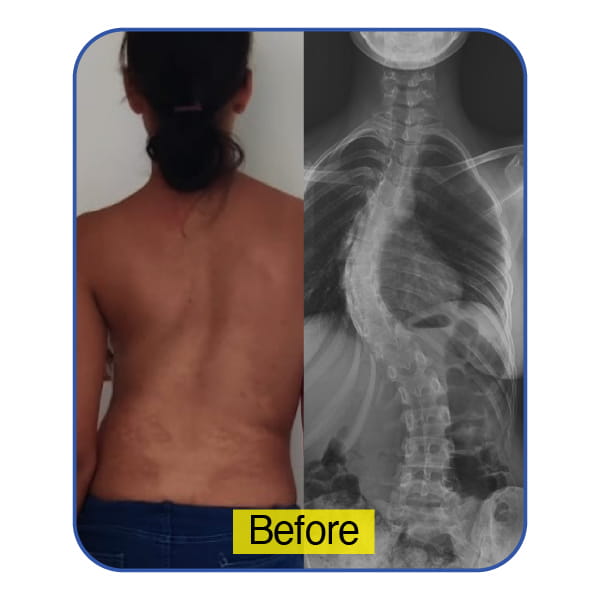

A 19-Year-Old from Seychelles – An Aspiring Swimmer’s Confidence Restored

For this young athlete from Seychelles, a noticeable spinal curvature began to interfere with her sporting aspirations and self-confidence. The deformity was becoming more pronounced, affecting posture, endurance, and comfort in fitted clothing.

Following comprehensive clinical assessment and precision surgical correction, spinal balance was successfully restored. She has since returned to swimming with renewed confidence and physical strength.